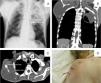

Un varón de 61 años de edad, fumador y sin antecedentes médicos de interés ingresó en el servicio de neumología por presentar inflamación supraescapular derecha de 4 meses de evolución y progresivo aumento de tamaño, acompañada de dolor intenso y limitación de la movilidad de la extremidad superior derecha. El paciente refería astenia y pérdida de peso en los 4 meses anteriores, pero no presentaba anorexia, fiebre ni molestias respiratorias. La analítica de sangre mostró una elevación de los marcadores inflamatorios sistémicos. La radiología de tórax (fig. 1) reveló una masa densa de tejido blando en la escápula derecha, y una cavitación con un nivel de líquido en la mitad superior del pulmón izquierdo. La TAC torácica (fig. 1) confirmó la presencia de una masa voluminosa que invadía la escápula derecha y los músculos adyacentes, y una masa pulmonar cavitada en el lóbulo superior izquierdo (véase la leyenda). El examen anatomopatológico de las lesiones mostró un carcinoma pulmonar de células escamosas poco diferenciado con metástasis en los tejidos blandos contralaterales. El estado general del paciente se deterioró progresivamente durante la hospitalización; aunque recibió el mejor tratamiento sintomático, el paciente falleció más adelante debido a la progresión de la enfermedad.

A) Radiografía posteroanterior del tórax: masa densa de tejidos blandos en la escápula derecha y cavitación con nivel de líquido en la mitad superior del pulmón izquierdo. B y C) TAC torácico (planos coronal y axial): masa heterogénea voluminosa de unos 110×94mm que invade la escápula derecha y los músculos adyacentes, con reacción del periostio escapular; y formación nodular heterogénea de aproximadamente 88×80mm, con cavitación central en el segmento apical posterior del lóbulo superior izquierdo, que invade la grasa mediastínica y la pared torácica. D) Fotografía de la masa supraescapular derecha tras la biopsia quirúrgica.